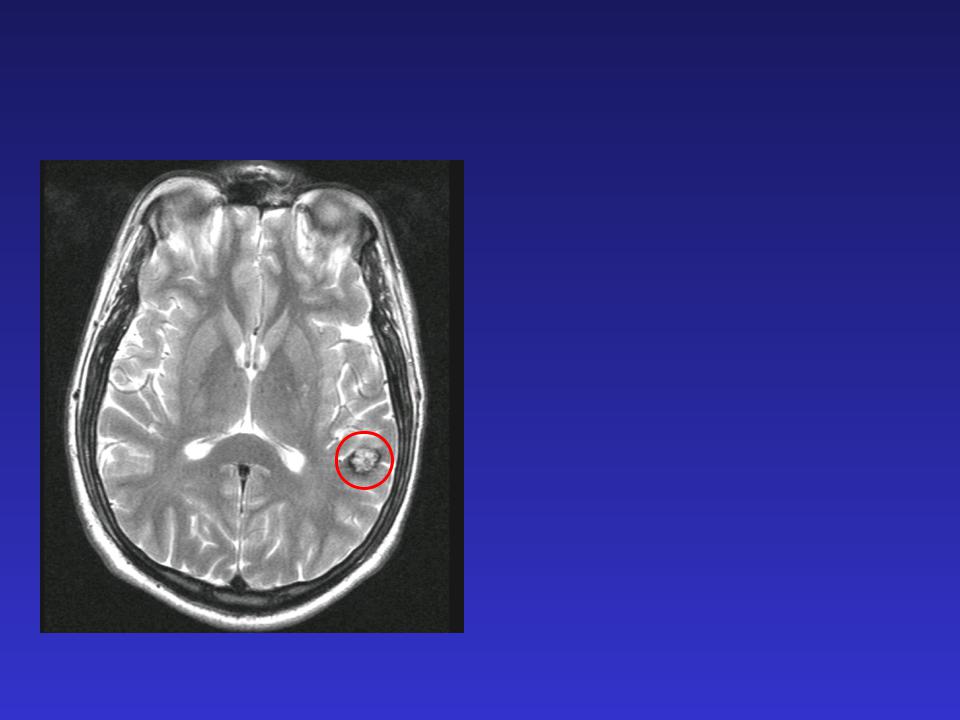

Мр картина венозной ангиомы левой гемисферы мозжечка - 96 фото